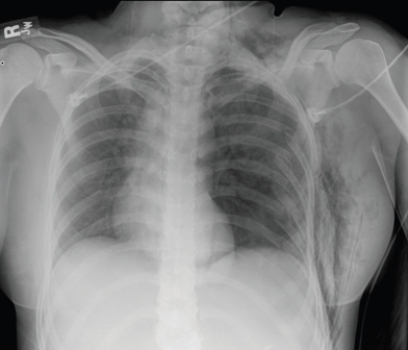

This portable AP chest radiograph shows a patient with: